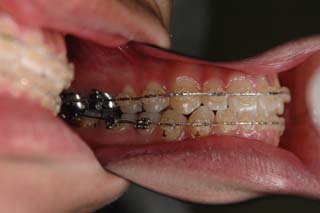

この症例では、目的外使用のオーソアンカー SMAPシステム が用いられています。

使用した主な装置名:TPB、マルチブラケット装置、オーソアンカー SMAPシステム

マルチブラケット装置でまっすぐに並べただけの状態です。なるほど、まるで噛めてない状態なのがよく分かります。ここでよく有りがちな矯正治療だと、上の前歯と下の前歯にゴムを1日中かけて噛ませていくのですが、それでは以前と同じく、関節をずらして噛むだけの人になってしまうでしょう。特に垂直的なコントロールが必要と考えられた上顎左側に オーソアンカー SMAPシステム の植立を行いました。